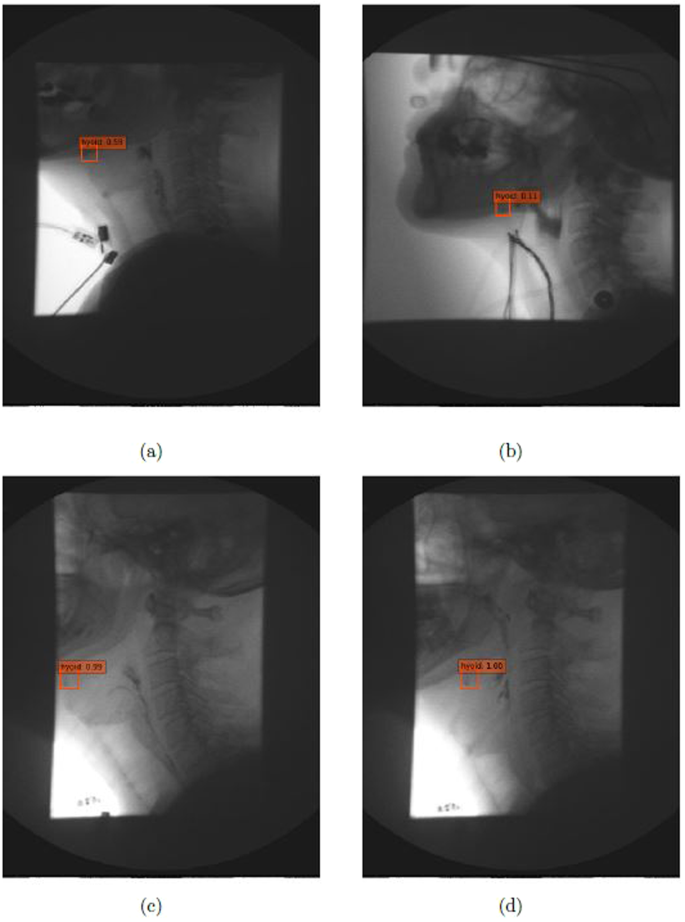

Figure 5 illustrates results using the SSD500-VGGNet method with different hyoid bone locations (under the mandible and behind the mandible), and the results are shown with different image qualities. From these results, SSD500-VGGNet showed stable detection results, clearly finding the hyoid bone. When the hyoid bone is hidden behind the mandible in case (a) and (b), the algorithm detected the hyoid bone with a relatively low confidence score. It performed well in case (c) and (d) where the hyoid bone is present under the mandible.

The hyoid bone moves upward and forward during a patient’s swallow. It will sometimes rise into the radiographic shadow of the mandible, obscuring its visibility by the judge/examiner. The judges must compare adjacent frames to infer the hyoid’s actual location when it is obscured by the mandible. Figure 5(a) and (b) show the detection of the hyoid bone. Although the confidence score is low, our algorithm can be considered successful because experts may not be able to locate the hyoid bone. Figure 5(c) and (d) are examples of blurred hyoid bone. The hyoid bone may be blurred when it moves quickly between two frames, but the algorithm can detect the moving hyoid bone with a high confidence score.